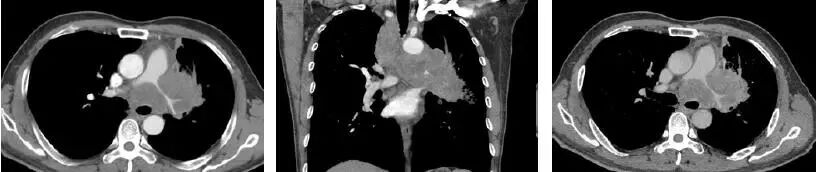

肿块,肺门增大,淋巴结肿大,并且,肿块和淋巴结互相融合,几乎是肺癌,大多数是小细胞肺癌。

肿块包绕肺动脉干,肺动脉干变细,纵隔、肺门可见明显肿大淋巴结,相互融合,与肺门肿块分界不清,形成“冰冻纵隔”,这种贪得无厌的肿瘤,几乎都是小细胞肺癌。假如病理科报道:鳞癌。你可以要求病理科做免疫组化,再看看片子,不要冲动

纵隔、肺门可见明显肿大淋巴结,相互融合,与肺门肿块分界不清,形成“冰冻纵隔”,几乎都是可恶的小细胞肺癌。